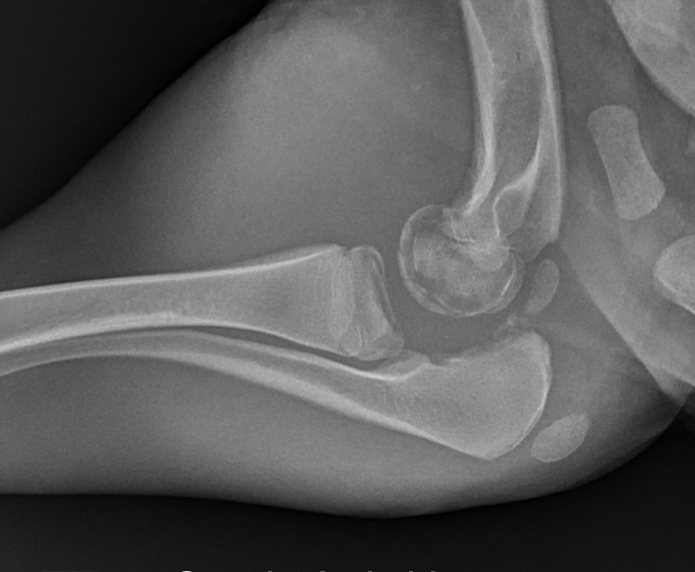

what wrong. Focal of systemic

1. Subluxation of tarsus from metatarsus

2. Increase distance in calcaneous joint

3. Soft tissue swelling

Systemic- involving more than one joint